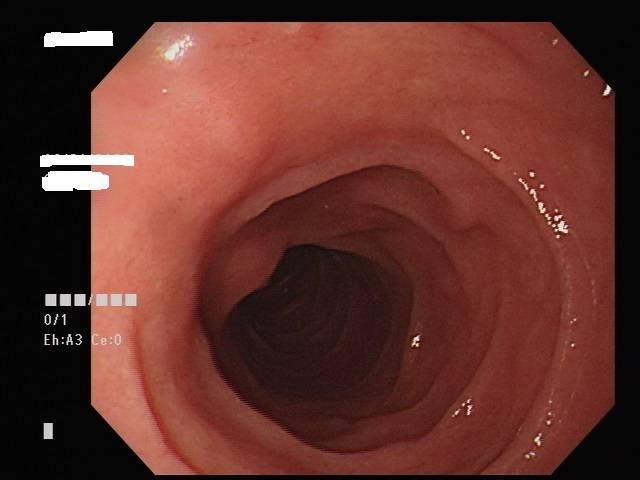

大腸鏡是一條黑色管子,由肛門進入依著大腸的走向,由下而上檢查:肛門→直腸→乙狀結腸→降結腸→橫結腸→升結腸。可以觀察整個大腸的任何病變,如:潰瘍、發炎、息肉、腫瘤及出血源,以進一步治療處置,如:息肉切除、切片、電燒止血等。

絕大部分的大腸息肉甚至是非常早期的大腸癌是可以用大腸鏡切除的,並不需要開刀。再將病灶送病理科切片檢查,將切片染色來判定是否為大腸癌,但大約都會需要2-3週的時間。大腸鏡檢查是動態的過程,在內視鏡於大腸內不斷往前推進的同時,有些息肉並不明顯,醫師是否能辨別每一個腸壁黏膜上的病灶,非常倚賴大腸鏡操作經驗和技術。